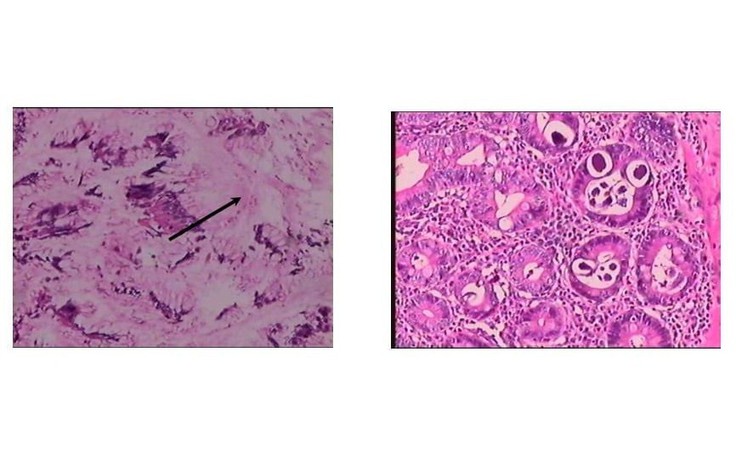

Người bệnh nữ (72 tuổi, ở TP.HCM) nhập viện Bệnh viện Nhân dân 115 (TP.HCM) vì đau bụng vùng thượng vị. Soi dưới kính hiển vi, bác sĩ phát hiện ra 'thủ phạm' thực sự là giun lươn.